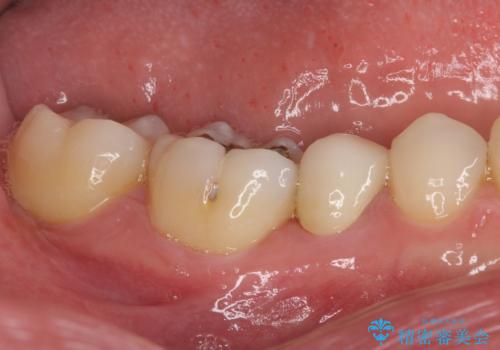

繰り返す痛み 下顎小臼歯の再根管治療

- 定期的に膿の出口ができ、食事の度に痛みを感じるとのことで来院された患者様です。

以前通われて医院にて、再度根管治療が必要であると伝えられていたようですが、レントゲン写真などの診察を行った結果、再根管治療が必要な状態でした。

レントゲン写真より、当該歯周囲に大きな透過像があり、歯槽骨が炎症により吸収している様子が認められます。

根管治療を行った歯はクラウンによる補綴治療が望ましく、来院時にはクラウンが装着されていなかったため、根管治療を再度行いやすい環境でした。

患者様と相談の上、再根管治療を行い、その後オールセラミッククラウンにて補綴治療を行うこととしました。

痛みが続く場合には、次の一手として歯根端切除術にて対応することを説明した上で治療を開始しました。